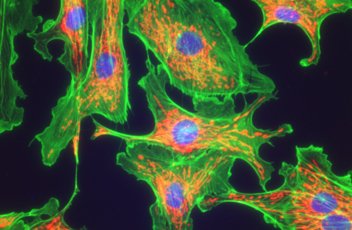

?落射熒光